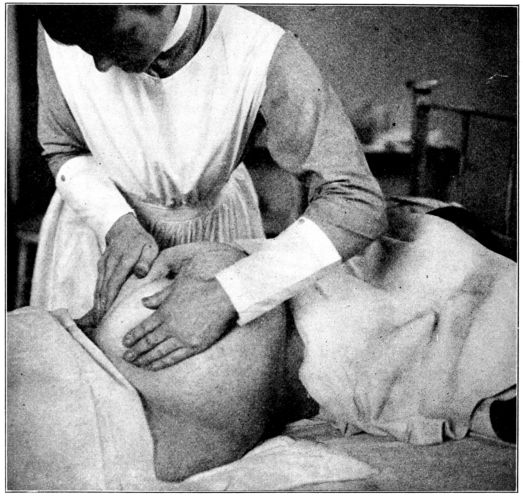

| 59. | Third maneuver in abdominal palpation | 227 |

| 60. | Fourth maneuver in abdominal palpation | 228 |